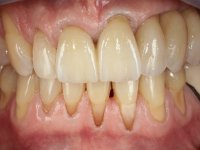

The patient comes to the consultation with a metal-ceramic bridge with great mobility. In addition to the near avulsion of the bridge, the patient was also interested in undergoing fixed oral rehabilitation, which improves aesthetics.

The patient was proposed to undergo a fixed oral rehabilitation consisting of a 2-element bridge over teeth 11 and 21 and a 5-element bridge over 3 implants that would be placed in the location of teeth 22, 24 and 26. The prosthetic structures would have an infrastructure in Zr coated with ceramic and the bridge over the implants would be screwed. The indicated extraction of teeth 25 and 26 and placement of an implant in the 26 site would imply surgery to fill the maxillary sinus. As the patient showed interest in having fixed temporary rehabilitation during treatment, we divided the treatment into 6 phases to achieve this goal: 1- Placement of a temporary bridge over teeth 11,21,25 and 26. With tooth extraction 24. 2- Placement of 2 implants in the location of teeth 22 and 24. 3- Placement of a temporary 6-element bridge over teeth 11 and 21 and over the implants. 4- Carrying out surgery to fill the maxillary sinus. 5 – Placement of the implant in the location of tooth 26 and in the area where the filling of the maxillary sinus was made. 6 – Placement of the definitive work.

A temporary acrylic bridge made in the laboratory with 7 elements was made, with teeth 11,21, 25 and 26 as pillars. The old bridge was removed and tooth 24 was extracted. The provisional bridge after relining was cemented in the mouth. Two implants were placed in the teeth 22 and 24 and 3 months after this intervention an impression was made to make a temporary bridge screwed over the implants and cemented to the teeth. The bridge was placed in the mouth and teeth 25 and 26 were extracted. 3 months later, surgery was performed to fill the maxillary sinus and 6 months later the implant was placed in the location of tooth 26. After osseointegration of this implant, the final impression was made for the final work. The bridge over the implants was permanently screwed on and the bridge over the teeth was cemented with resin-reinforced glass ionomer cement.